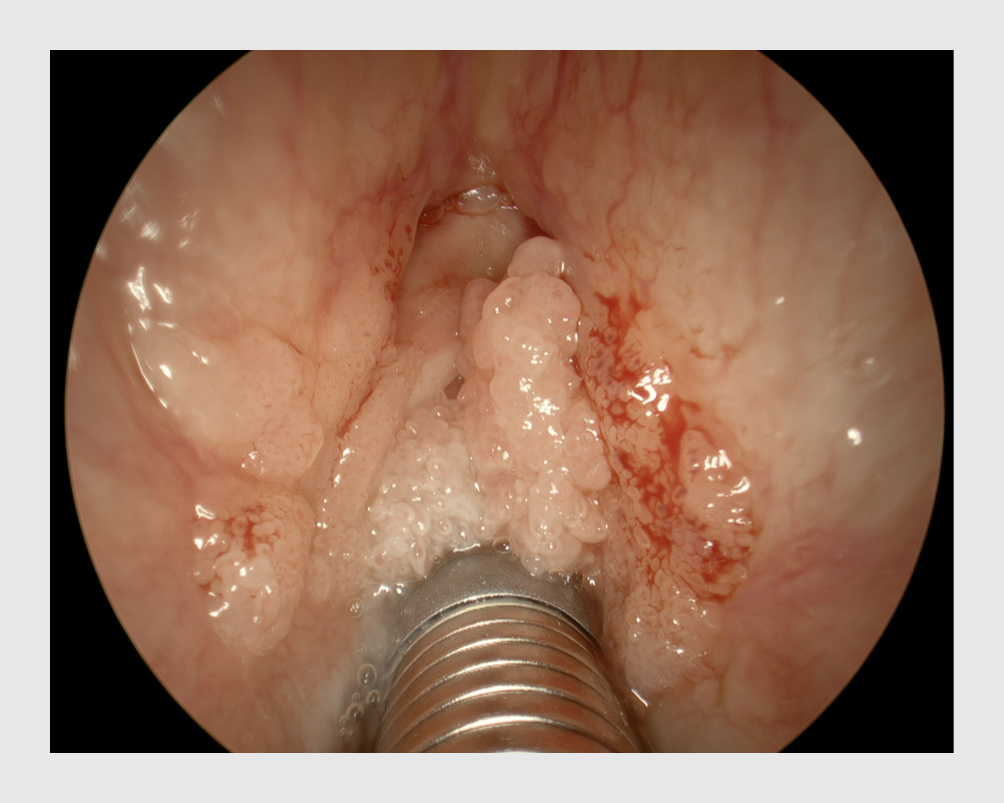

Recidiverende respiratoire papillomatose, ook wel larynxpapilloom, is een chronisch ziekte die geïnduceerd wordt door het humaan papillomavirus (HPV). Hierbij vormen zich wratachtige afwijkingen in de luchtwegen. Patiënten ontwikkelen dysfonie, hoesten en uiteindelijk dyspneu. Er is geen curatieve behandeling, en vaak is veelvuldig operatief ingrijpen nodig om de luchtwegen vrij te houden.

Een 25-jarige patiënte had ondanks het Rijksvaccinatieprogramma tegen HPV-geïnduceerde ziekten toch larynxpapilloom ontwikkeld. Zij moest 11 operaties in 5 jaar ondergaan. Praten koste haar moeite en dit leverde veel sociale problemen op.